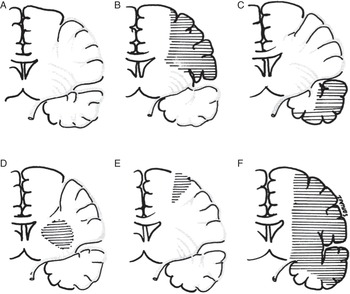

Caplan's Stroke: A Clinical Approach: 9781107087293, Large artery occlusive disease of the anterior circulation,

Large artery occlusive disease of the anterior circulation, 81ctn1kPzML.jpg,

81ctn1kPzML.jpg, Large artery occlusive disease of the anterior circulation,

Large artery occlusive disease of the anterior circulation, Uncommon Causes of Stroke: 9781107147447: Medicine & Health,